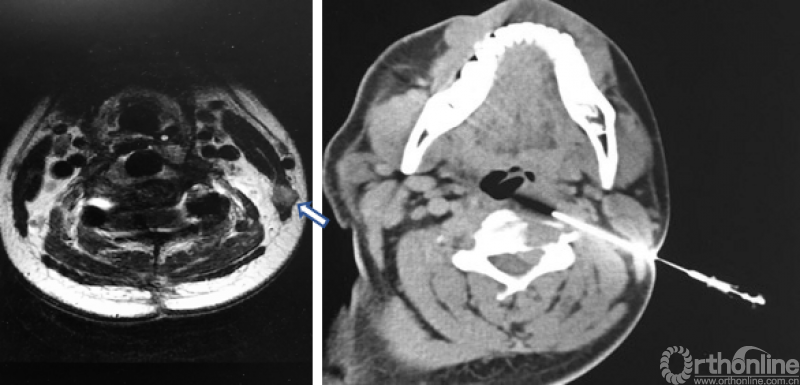

图1,颈椎MRI和CT

病人的核磁和CT显示了一个以C3-4椎间孔为中心的哑铃型肿瘤,并且伴有C3和C4椎体的骨质破坏(图1)。这些片子给我的第一印象也是神经源性肿瘤。伴有椎体破坏的神经鞘瘤并不少见,比如下面这个病例就是一个经过手术证实的累及椎体的哑铃形神经鞘瘤(图2)。